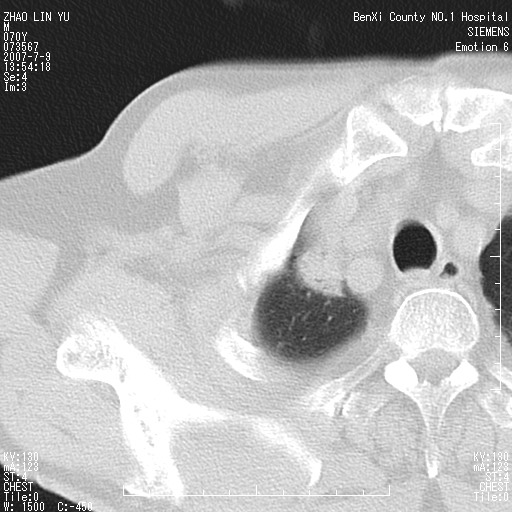

以下是引用王靖旗在2007-7-10 17:12:00的发言:[br] 男、70、咳嗽两个月,半年前换瓣手术,胸片未见异常,于昨天行x片发现右肺上野大片影,行ct扫描,这里是减薄图像,余肺正常。明天晚上会有增强扫描片,到时我会上传。[br][br] 冠状位请大家细看,应该是有意义的,[br][br] 请大家先看平扫发表意见。[br][br]

以下是引用zhangzhongshou在2007-7-10 21:43:00的发言:[br]右肺上叶周围型肺癌,以孤立型细支气管肺泡癌可能性大。